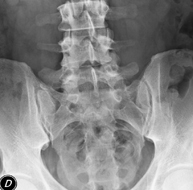

- Spinal teleradiology

This technique uses X-ray rendered imaging to examine the entire spinal column, especially assessing the presence of scoliosis and pelvic dysmetria.